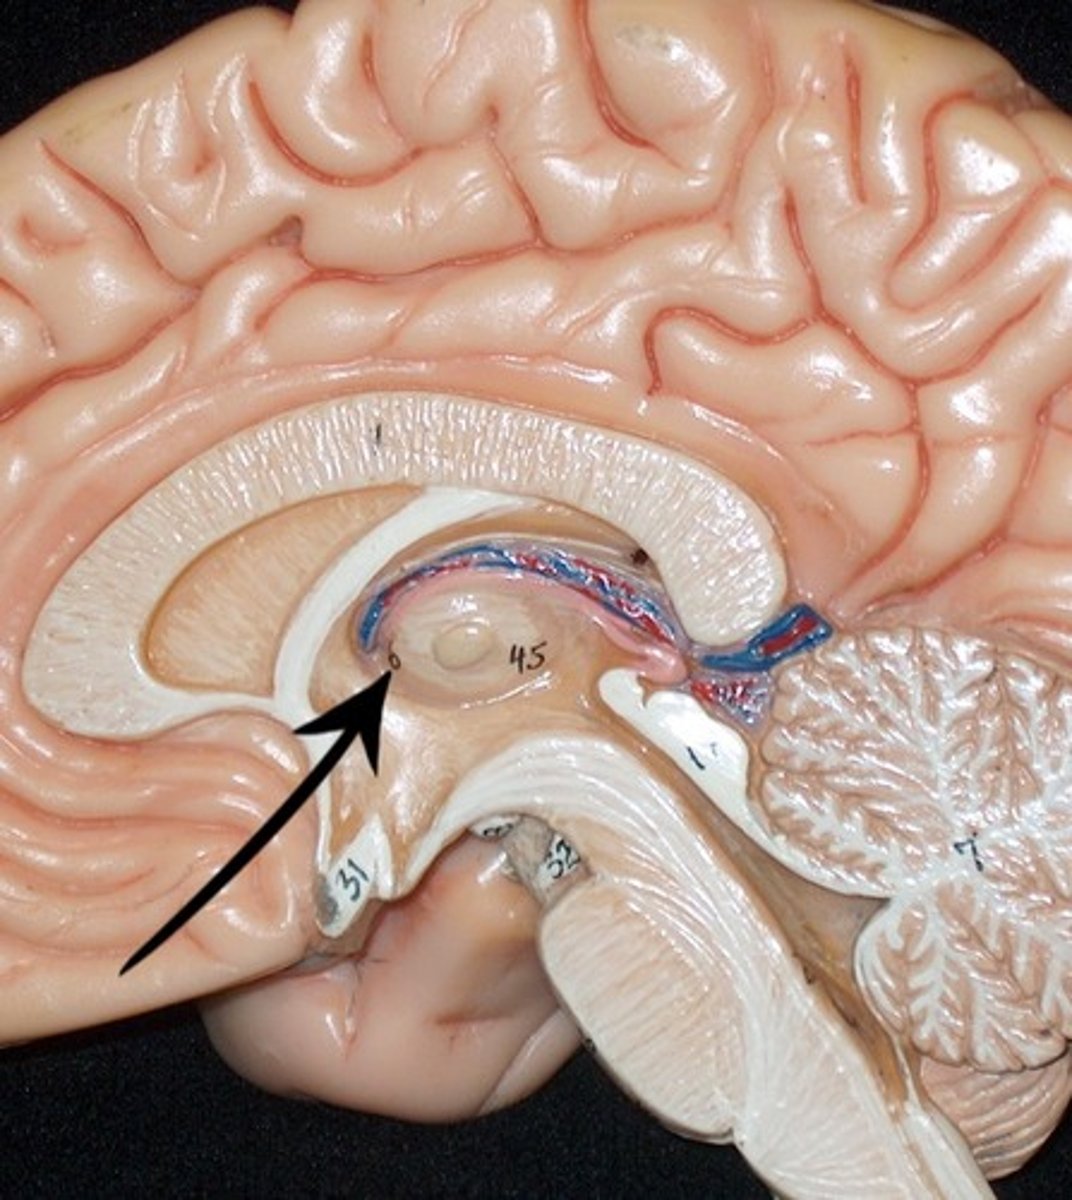

corpus callosum

fornix

intermediate mass of thalamus

choroid plexus (of ventricles)

third ventricle